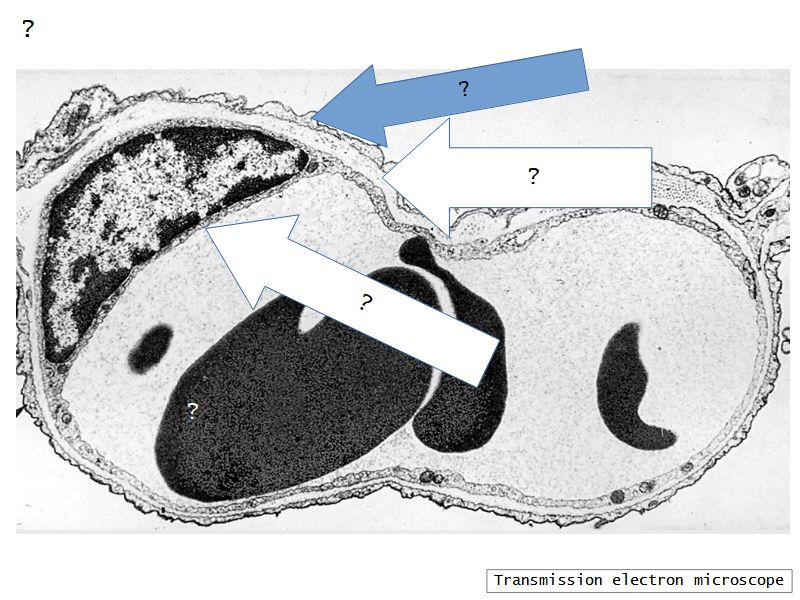

Fill in all the missing labels, and assess as you move through the slides. Answers on the down slide. It is important to do this using pen and paper, and not just glance through the images.